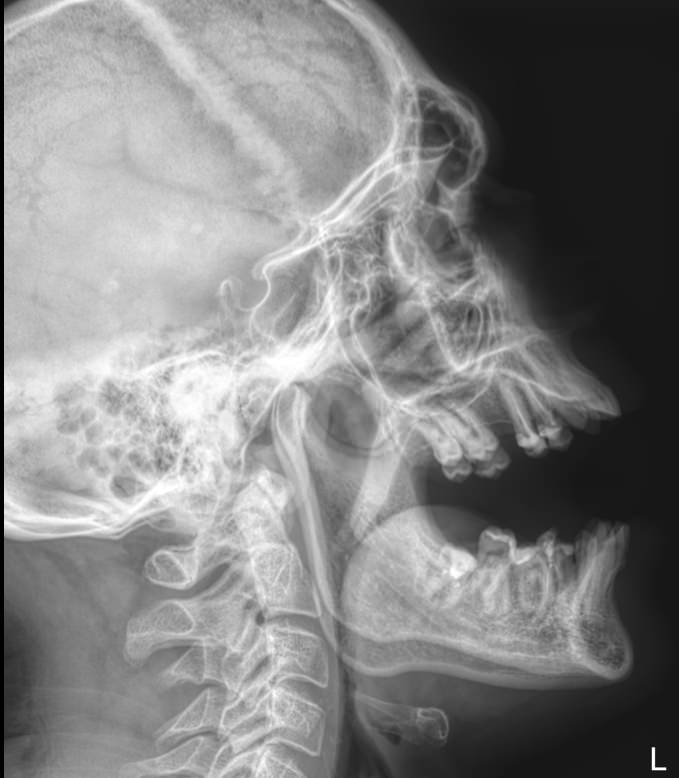

Первый вид обследования, который чаще всего назначают при подозрении на заболевания гипофиза ― рентгенография. На снимке будут четко видны изменения, которые позволят врачу выбрать способ лечения или дополнительные виды обследования.

Что покажет рентген хиазмально-селлярной области

• Изменение стенки: истончение, разрежение, выраженная деструкция;

• Дно: без изменений, неровный внутренний контур, углубленное;

• Клиновидные отростки: могут быть тоже истонченные;

• Внутренний контур: неровный, «двойной»;

• Могут быть изменены нормальные размеры: сагиттальный, вертикальный и их соотношение ― индекс седла.

Специально готовиться не надо. Однако необходимо снять с головы и шеи все металлические предметы: цепочки, заколки, серьги, съемные протезы и предупредить о несъемных. Также надо снять очки и расстегнуть верхние пуговицы на одежде. Затем надо надеть свинцовый фартук и сесть или встать к регистрирующей пластине боком. Снимок выполняется в боковой проекции, реже ― в прямой, как именно приложить голову, покажет рентгенолаборант.